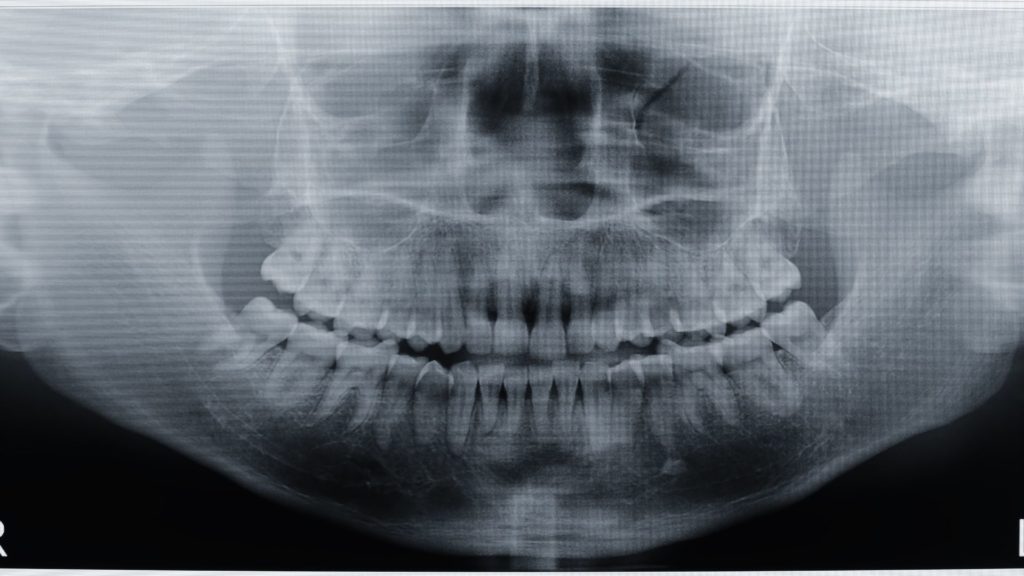

In some cases, extraoral X-rays are used, such as panoramic X-rays, which show all facial structures related to the mouth, or Cone Beam Computed Tomography (CBCT), which provides 3D images of the mouth, upper jaw, and lower jaw. These images are ideal for:

- Evaluating fractures

- Analyzing infections

- Reviewing periodontal diseases

- Planning complex treatments